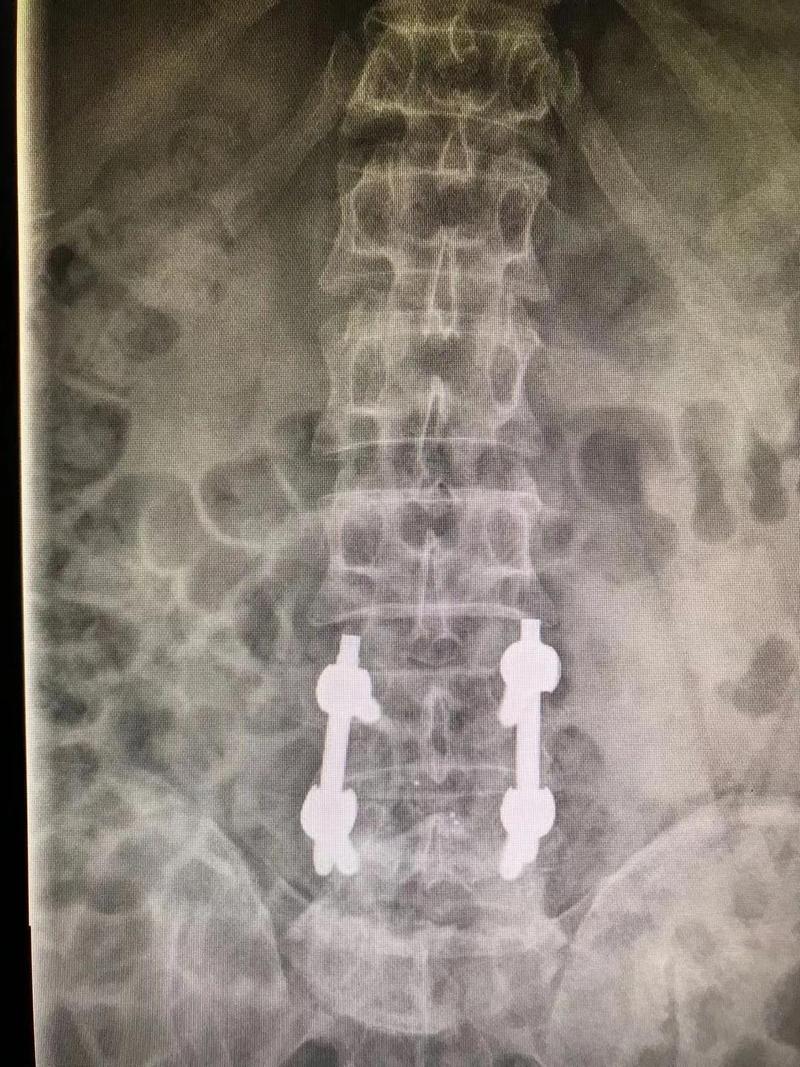

术前

经过周密的术前评估及患者意愿,张昊主任决定利用UBE技术为叶先生进行治疗。

术后

与开放外科手术相比,UBE技术只需切两个1cm大小的切口,通过肌间隙进入,创伤明显减少,术中出血少。对椎旁肌肉损伤较小,且能够最大程度地保留完整的脊柱结构,维持了术后脊柱的稳定。术后效果立竿见影,并发症少,恢复快,对术后活动几乎没有影响。

■ 腰椎融合术

是通过植入一些器械(如融合支架或者椎弓根螺钉)使上下两个锥体融为一体,不能再相对活动。一般来说不作为首选手术,只适用于以下情况:腰椎间盘突出症伴明显的慢性轴性腰背痛;巨大椎间盘突出、腰椎不稳;复发性腰椎间盘突出,尤其是合并畸形、腰椎不稳或慢性腰背痛的情况。